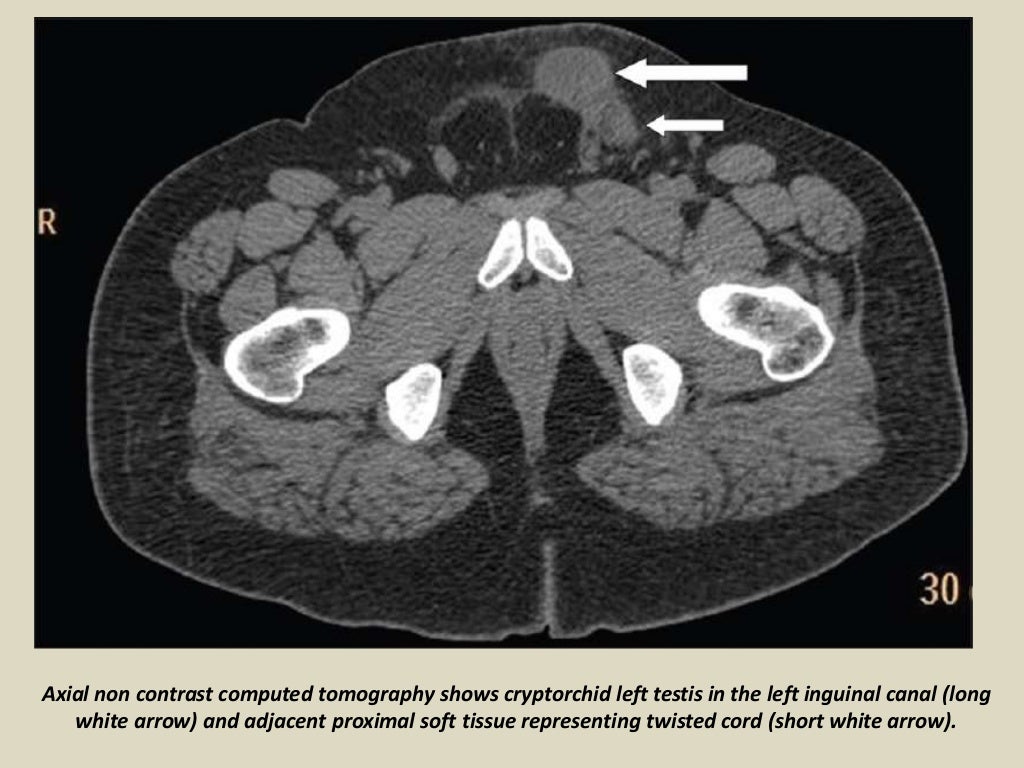

Presentation1, radiological imaging of undescended testis. What Is Undescended Testes In Tagalog These are the testes and. Male reproductive system diseases account for 14% of the burden of health in filipino men. And 10% of the time, it’s bilateral or affecting both testes. Instead, it’s in the groin or lower abdomen. Undescended testes is when one or both of the male testes have not passed down (descended) into the scrotal sac. Cryptorchidism. What Is Undescended Testes In Tagalog.